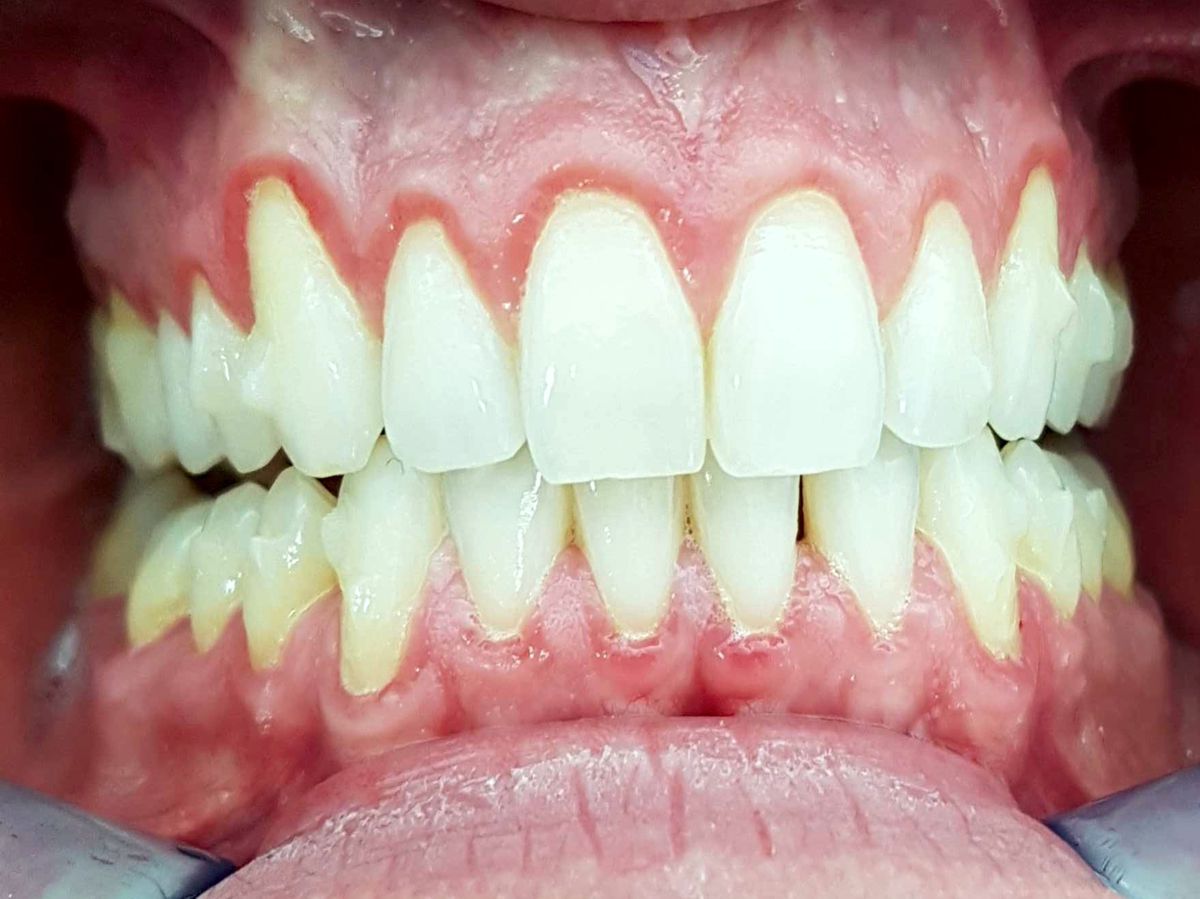

Die Zahnhälse sind gerötet und empfindlich, bluten rasch.

Sofern der Zahnhals freiliegt sind die Zähne dunkel verfärbt (Schwarz ist die Farbe des Todes). Bei diesem Zahn ist auch noch eine Silberkrone zu erkennen, was unter Umständen die Giftigkeit des Zahnes noch weiter erhöht.